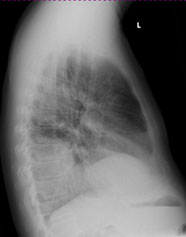

Radiologie Quiz 47

Ein 68-jähriger Patient mit chronischer Niereninsuffizienz und hypertensiver Herzerkrankung klagt akutell über zunehmende Dyspnoe. Sie veranlassen ein Thoraxröntgen.

Thorax seitlich

Welcher Befund liegt vor? (mehrere richtige Antworten möglich)